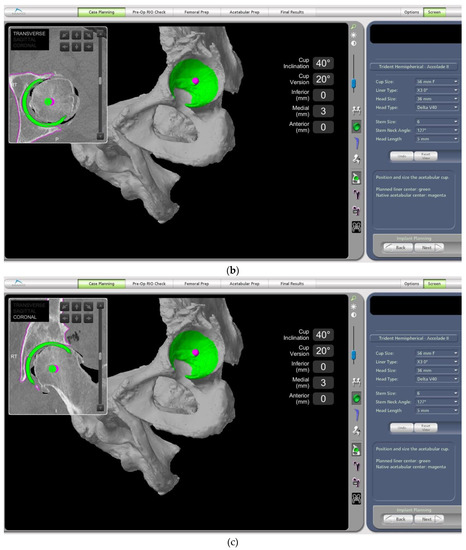

- In this case, the native femoral retroversion (−6 degrees) posed a challenge in avoiding impingement (Figure 7). Upon assessing VROM, bone-on-bone and implant-on-implant impingement in deep flexion were noted (Figure 8). Using the robotic software, the planned femoral version was corrected to +16 in the femoral broach (Figure 9a,b).

- VROM was performed again, and impingement in flexion was eliminated (Figure 10). In extension, upon subtracting the femur, it became apparent that there was a small area of impingement secondary to an anterior osteophyte which was planned to be removed after cup insertion during the operation (Figure 11a,b).